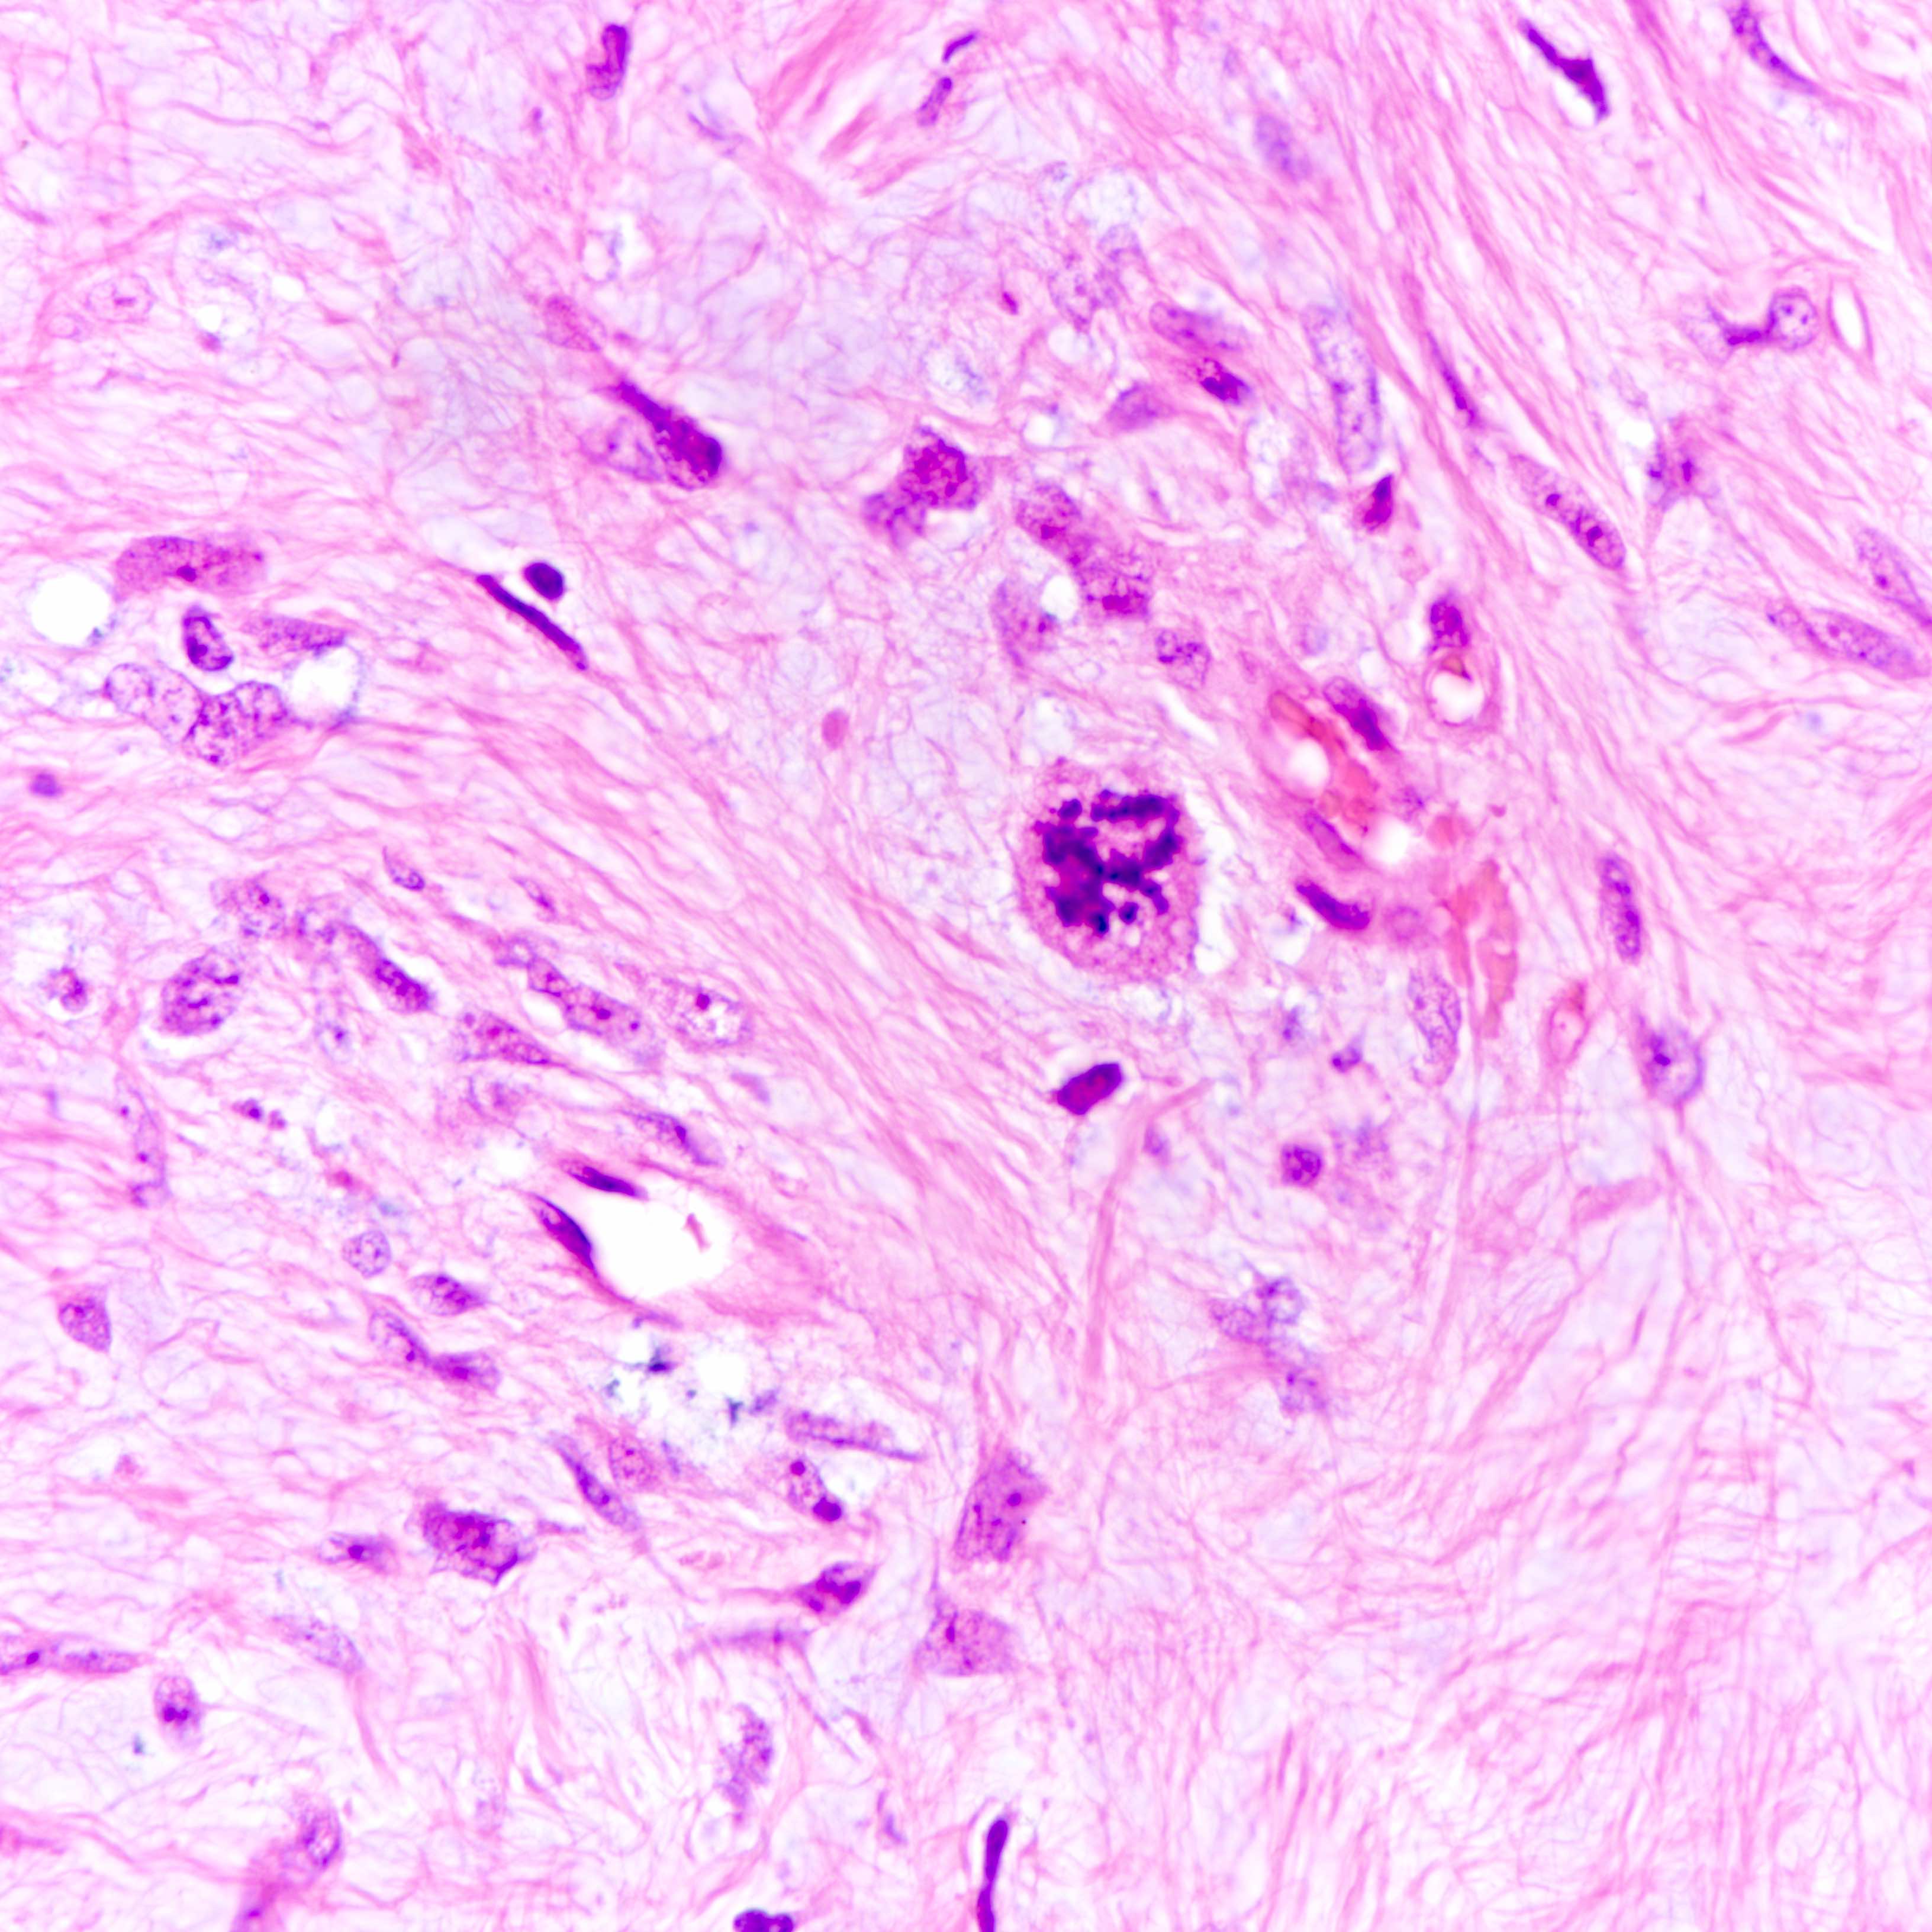

Microscopic (histologic) images

Contributed by Joshua J.X. Li, M.B.Ch.B. and Gary M. Tse, M.B.B.S.

Malignant phyllodes tumor